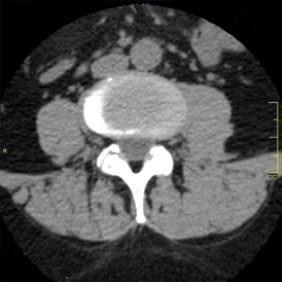

Tomografía computarizada Columna

< Volver a "Tomografía Computarizada (TC) con Inteligencia artificial"Con esta prueba valoraremos la patología de las vertebras, fracturas, hernias, protusiones discales,…